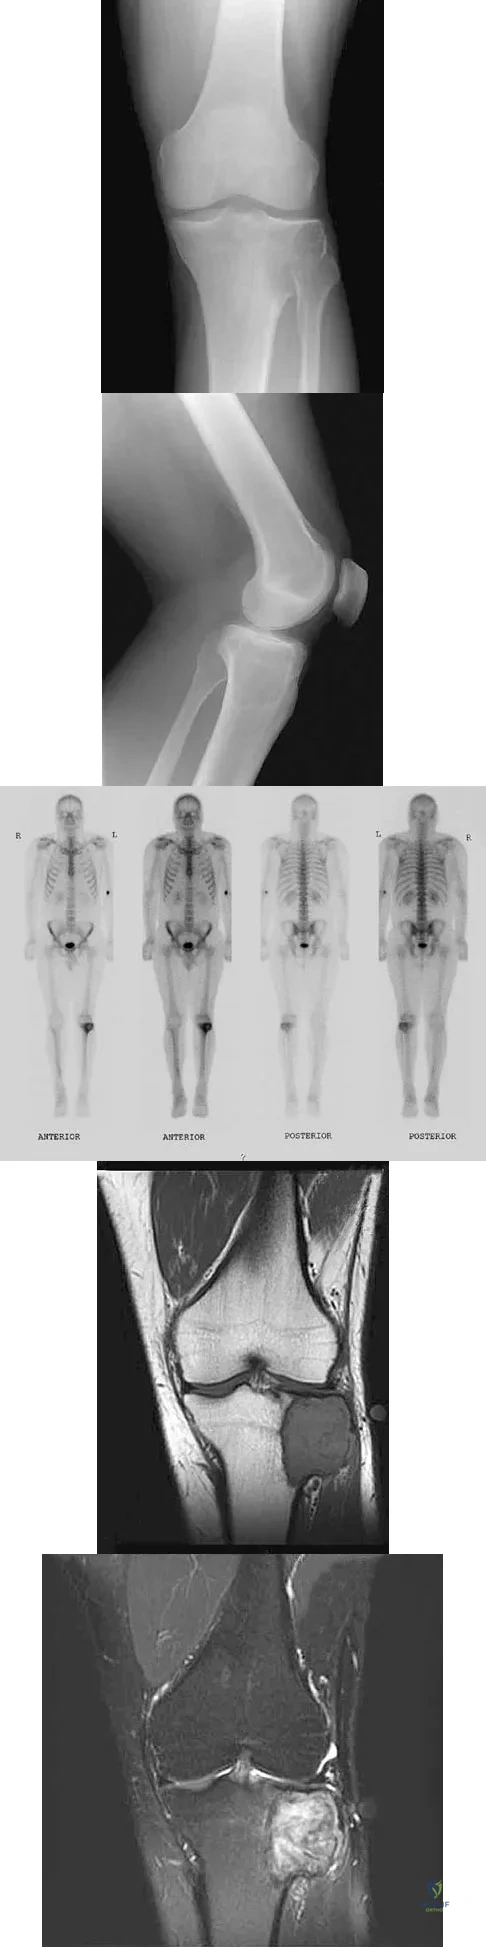

Question 85

A 24-year-old man has had pain in the left knee for the past several months. He reports that initially the pain was associated with weight-bearing activities, but it has now become more constant. He denies any swelling but reports a lateral fullness at the tibial plateau. Figures 23a through 23e show radiographs, a bone scan, and T1- and T2-weighted MRI scans. What is the most likely diagnosis?

Explanation